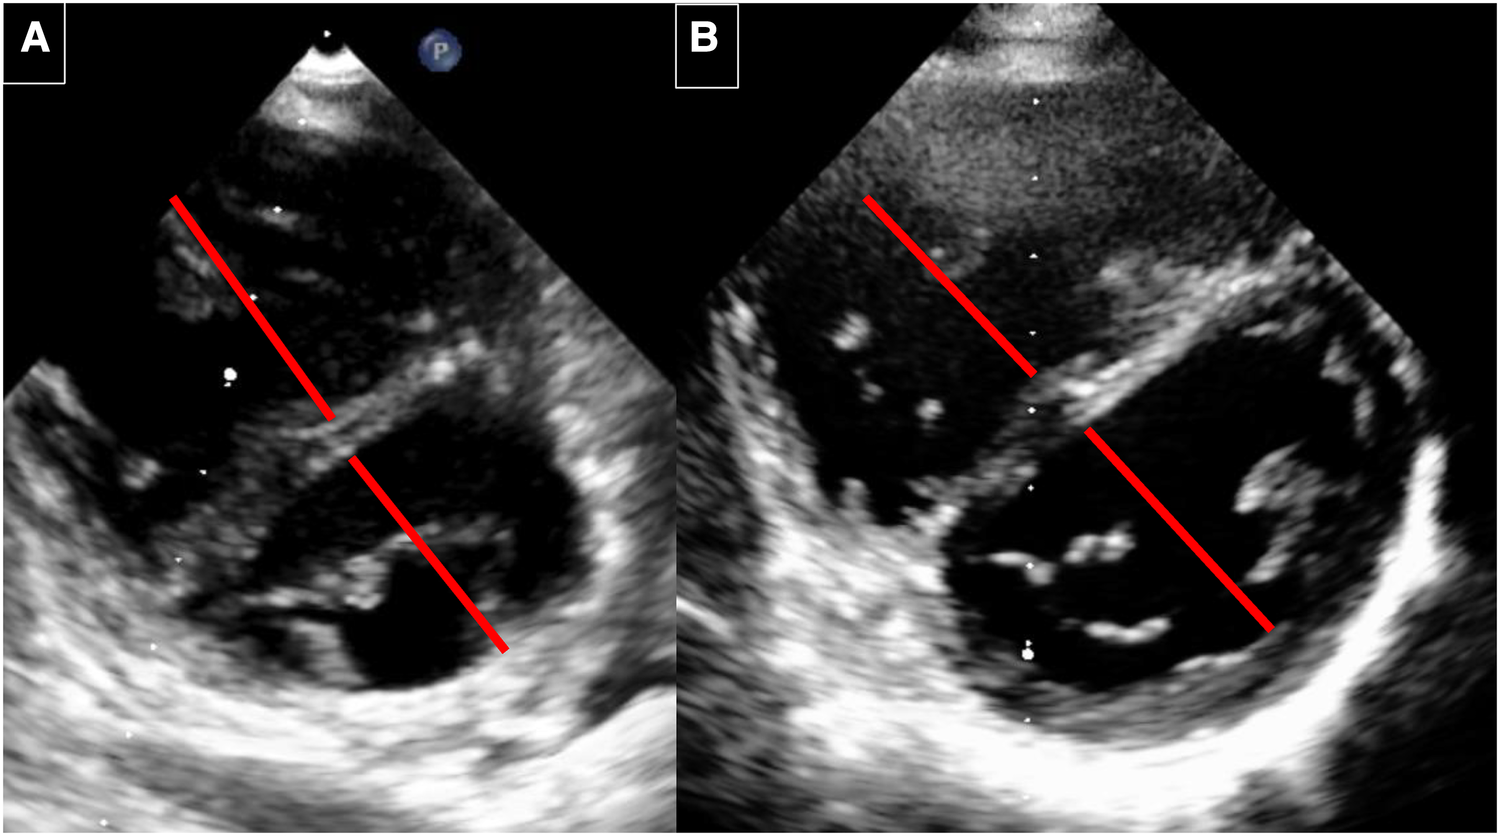

After the AFR device (Occlutech, Germany) implantation, she recovered within 1 day and never developed syncope again. In the following two years, a normalisation of the saturation over 95% could be observed, her NTāpro BNP levels went back to normal values, and her exercise capacity increased. The saturation drops to around 75% under exercise conditions. The cardiac catheterisation 3 years after AFR device implantation showed significant improvement (TableĀ 1). 6 years after device implantation, her baseline saturation remained normal (98%, NHYA functional class II), the right ventricular volume and size decreased (FigureĀ 4), NTāpro-BNP values were satisfying (TableĀ 2) and the 6-minute walking distance was around 540ā m.

Figure 4

Echocardiography before and 6 years after implantation. (A) Before implantation: RV with septal flattening before AFR implantation. The RV/LV diameter ratio is 1: 0.87. (B) 6 years after AFR implantation. RV with decrease of the RV volume and improved LV filling. The RV/LV ratio is 0.87/1.